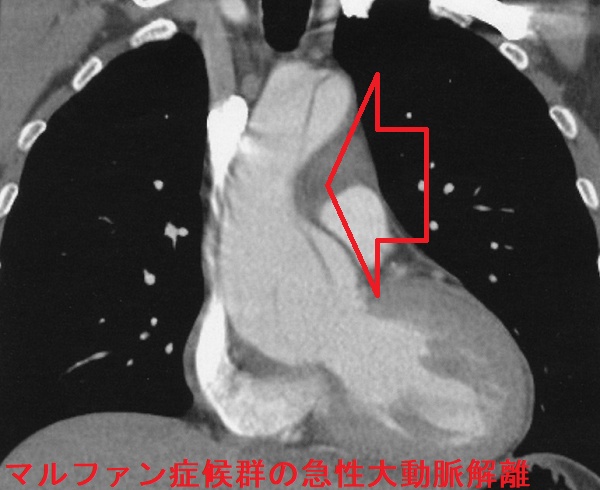

マルファン症候群(marfan syndrome:MFS)は、常染色体優性遺伝性の結合組織異常。フィブリリン-1(fibrillin-1)をコードするFBN1遺伝子やTGF-β 受容体遺伝子の突然変異が原因で、過剰TGF-βの臓器沈着からコラーゲン形成障害が生じます。

マルファン症候群の身体的特徴として、高身長で四肢の指が長い、胸郭の変形、眼の水晶体亜脱臼などがあります。

マルファン症候群で特に問題となるのが大動脈壁の脆弱性で、

- 大動脈弁輪拡張による大動脈弁閉鎖不全症(AR)

- 大動脈瘤、急性大動脈解離がおきると命にかかわる

通常の急性大動脈解離は60歳以上の高齢者に多いが、マルファン症候群では20歳-30歳代に発症することが多い。激しい運動はマルファン症候群の脆弱な動脈壁を破綻させるため禁忌。

マルファン症候群の急性大動脈解離 胸部造影CT 水平断像;矢印はflap